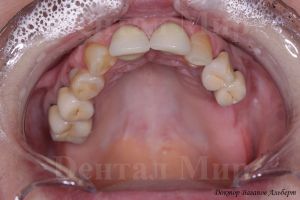

Верхняя и нижняя оклюзионные фотографии показывают общую ситуацию: отсутствующие зубы, их расположение и смещение.